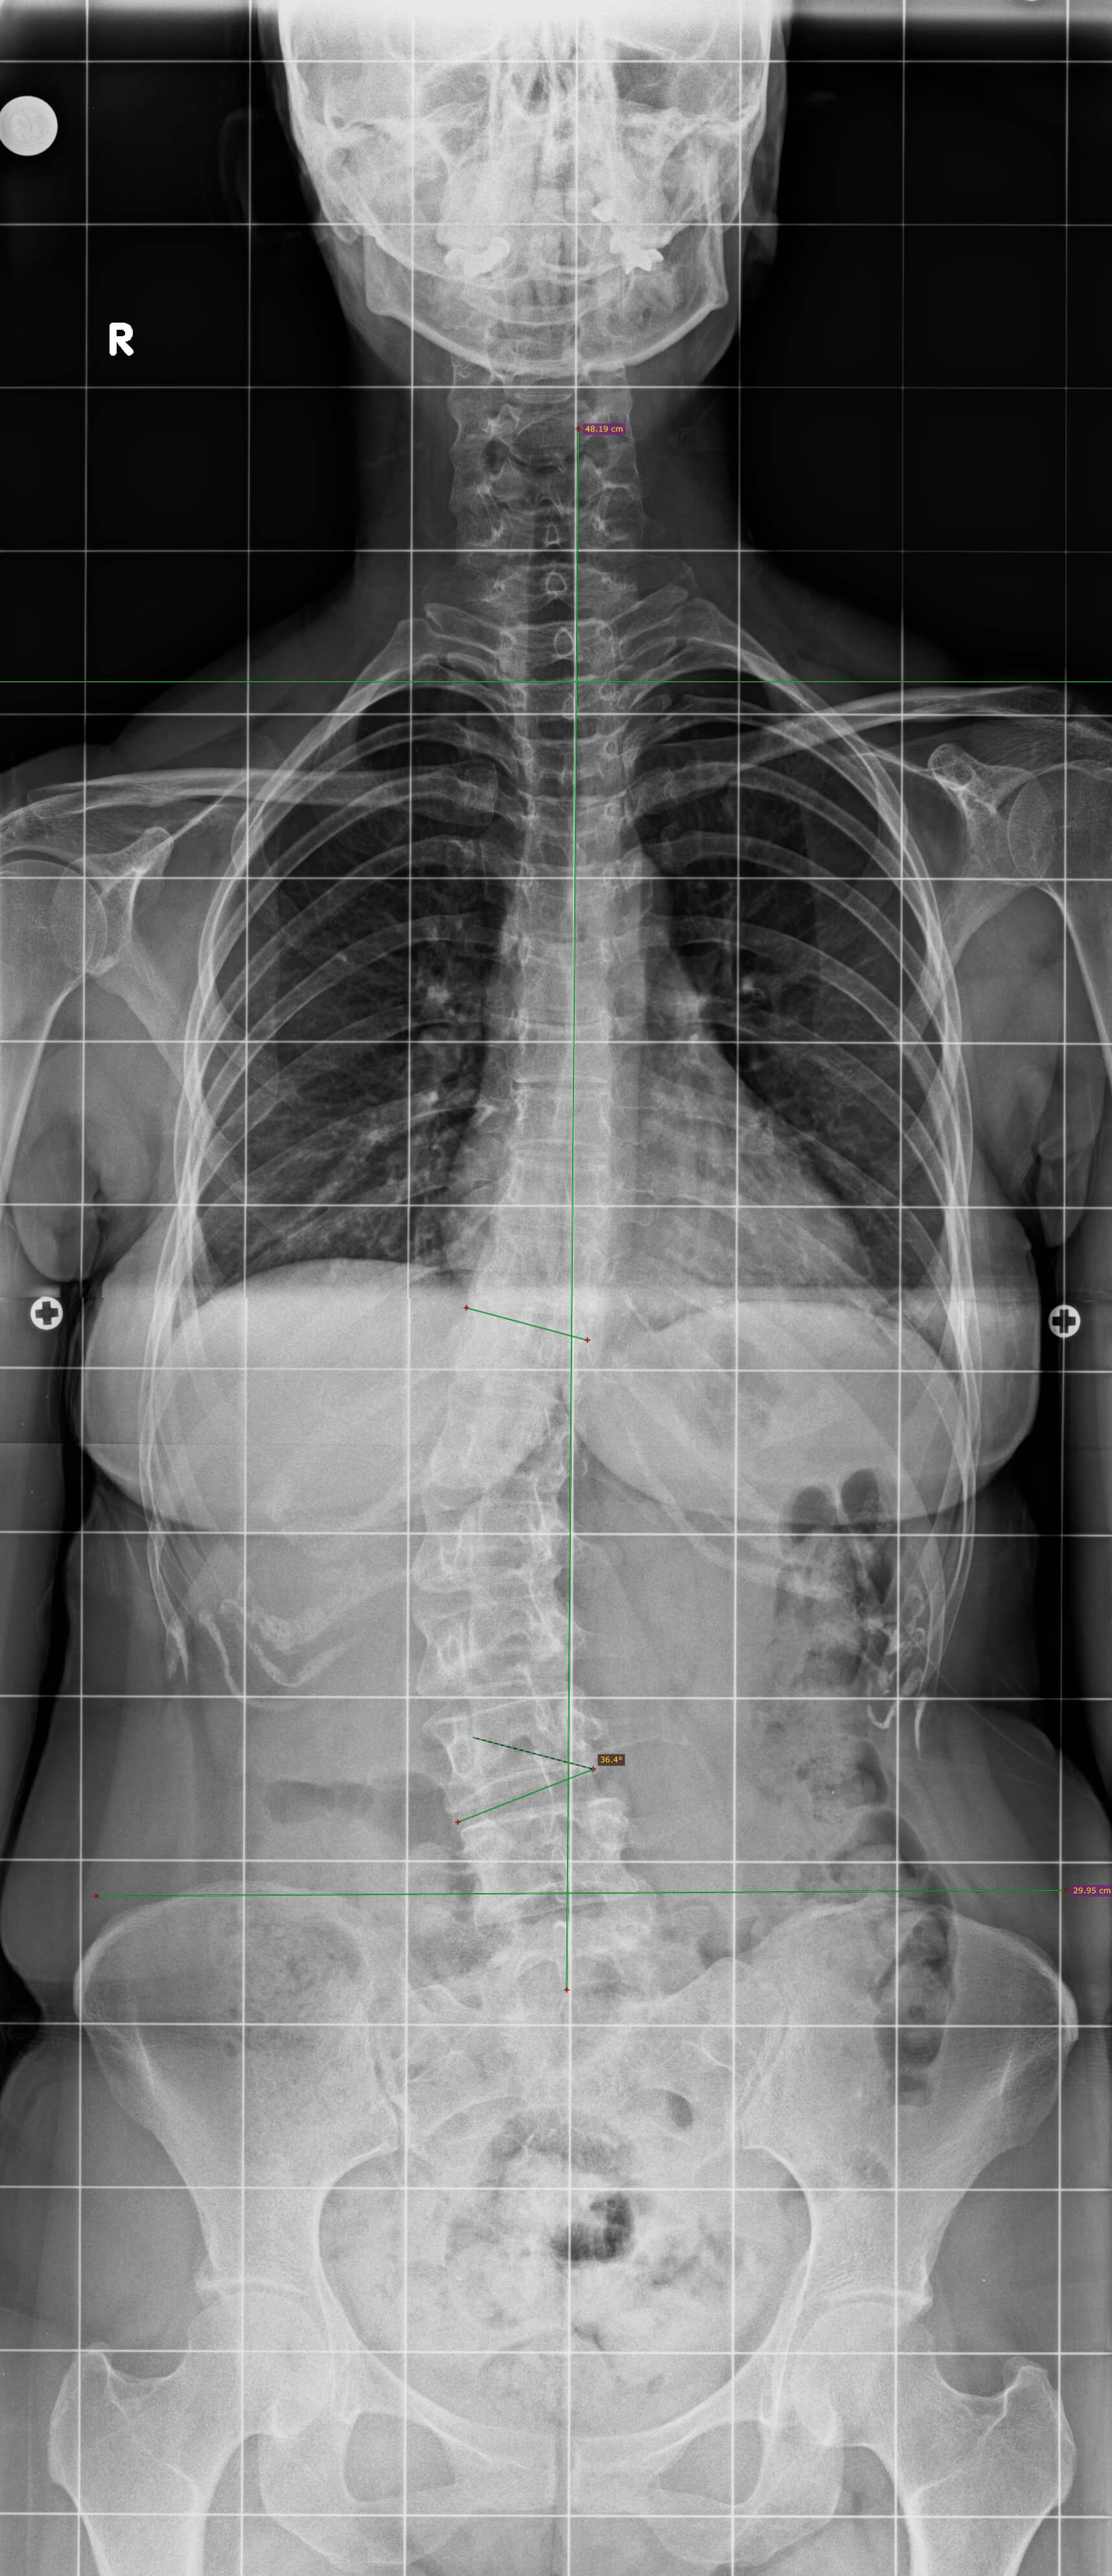

26 yaşında kadın hasta. Sırt ve bel ağrıları mevcut.

Ameliyat Öncesi